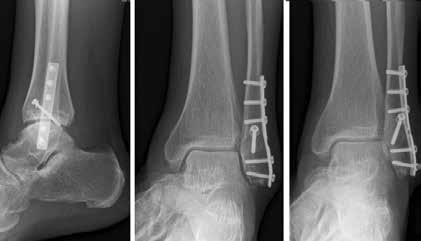

Endoprothetik des OSG

Die Indikation zur endoprothetischen Versorgung einer OSG-Arthrose ist gründlich zu stellen. Darunter fällt die schwere Arthrose jeglicher Ätiologie mit täglich intensiven Schmerzen, hochgradigem Gelenkfunktionsverlust und Gelenkdestruktion. Voraussetzungen sind eine gute Knochenqualität sowie mittleres Alter ohne schwere systemische Vorerkrankungen. Auch bei der Implantation von Endoprothesen des oberen Sprunggelenkes ist es wichtig, bestehende Achsfehlstellungen entweder in gleicher Sitzung oder zuvor zu korrigieren. Sofern nach Achskorrektur die Versorgung mittels einer Endoprothese noch notwendig ist, soll damit die Funktionsfähigkeit des Gelenks, eine Schmerzeliminierung und eine Verbesserung der Lebensqualität erreicht werden (Abb. 6). Kontraindikationen sind neben den bereits oben genannten: bestehende Osteonekrosen, periphere arterielle Verschlusskrankheit, periphere Neuropathie, bestehende oder stattgehabte Gelenkinfektion und schwere Bandinstabilität 56.